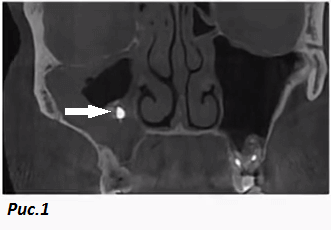

Инородное тело в правой гайморовой пазухе интенсивно контрастирует на компьютерной томографии, указано стрелкой. Вокруг него менее интенсивная обширная тень, указывает на утолщение слизистой пазухи. Кстати на другой стороне видно как корни зубов могут сообщаться с полостью пазухи. Фото для примера из Интернета.